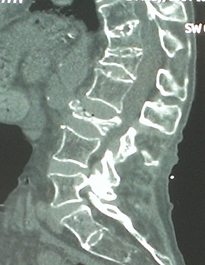

因:“腰椎骨折椎体成形术后2天”入院

患者因“脑卒中后遗症”在我中心康复治疗,于4月27日行走时滑倒腰部跌伤,当时即感疼痛,活动受限,到当地医院就诊,经CT等检查后,诊断为L3骨折,予卧床休息、口服活血化瘀及镇痛等对症治疗,患者自觉症状无改善,于6月03日在上级医院行椎体成形手术,2014年6月04日再次转入我中心继续康复治疗。患者入院时腰背部疼痛明显改善,并可下床活动。

神清,精神可,轮椅推入病房,精神略显紧张,发育正常,营养中等,呼吸平稳,查体合作,言语清晰,对答切题。全身皮肤粘膜无黄染,无皮疹、无淤斑、淤点,毛发分布正常,皮温正常、皮肤弹性正常,无肝掌。浅表淋巴结未及肿大。头颅大小正常,无畸形,眼睑无水肿,结膜无充血,眼球正常,无运动障碍,巩膜无黄染,角膜正常,双侧瞳孔等大等圆7.5px,对光反射正常。左侧鼻唇沟浅,左侧口角下垂,左侧额纹消失,耳廓正常,外耳道无脓性分泌物,乳突无压痛,双侧听力正常。鼻外形正常,鼻道畅,鼻中隔无偏曲,鼻旁窦无压痛。口唇红润无绀,口腔粘膜正常,舌正常,伸舌居中,牙龈无肿胀出血,咽无充血,双侧扁桃体未见肿大,声音正常。颈软,无抵抗,脑膜刺激征阴性,气管居中,颈静脉无充盈,双侧甲状腺未及肿大,无压痛。胸廓无明显畸形,乳头对称,双侧呼吸运动对称,语颤相等,叩诊清音,双肺呼吸音粗,未及明显干湿啰音。心前区未见异常隆起,心尖搏动位于左第5肋锁骨中线内12.5px,未及震颤,心相对浊音界正常。心率80次/分,律齐,各瓣膜听诊区未闻及病理性杂音。未及水冲脉、股动脉枪击音。腹平,未见腹壁静脉曲张,未见肠型蠕动波,腹软,无压痛、反跳痛,肝脾肋下未及,肾未触及,全腹未触及包块,肝肾区无叩痛,移动性浊音阴性,肠鸣音正常,5次/分。脊柱胸腰段后凸畸形,活动度轻度受限,棘突无明显叩痛,双下肢无水肿。四肢肌力正常,关节无畸形。双下肢感觉正常。

入院诊断:(1)腰椎骨折术后